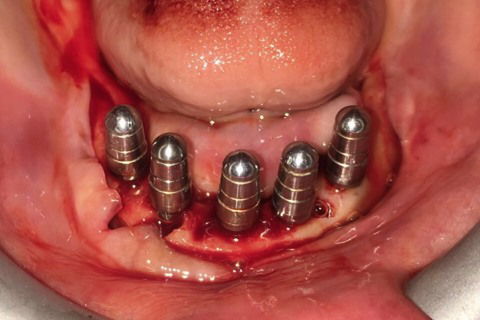

Paciente com síndrome de kelly,foi feito exodontia do 33 ao 43,regularização da tábua óssea e colocação de 5 implantes Implacil UN2 cônicos HI de 4x12,em seguida foi feito procedimento protetitico.

Fotos do caso